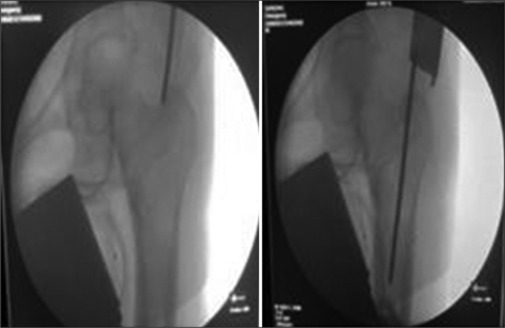

Background: Proximal Femoral Nailing (PFN) and Proximal Femoral Nailing Anti-rotation (PFNA 2) are both intra-medullary implants having 6 degrees of proximal valgus angulation. The helical blade compact the cancellous bone in femoral head when it is driven inside.

Materials and methods: The study was conducted from October 2021 to September 2022 which included 76 patients of unstable intertrochanteric fractures of femur.

Conclusion: PFNA 2 significantly reduces the operative time and blood loss compared to PFN. However Both PFN and PFNA 2 implants offers no statistically significant advantages over each other in terms of fracture unions, functional and radiological outcomes, post-operative complications and recovery outcomes.